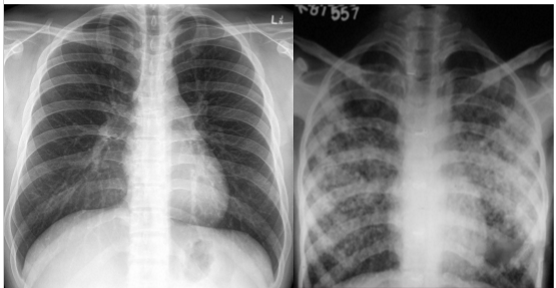

What is going on in these pictures. Whats the dx?

Left pic: normal

Right pic: COPD